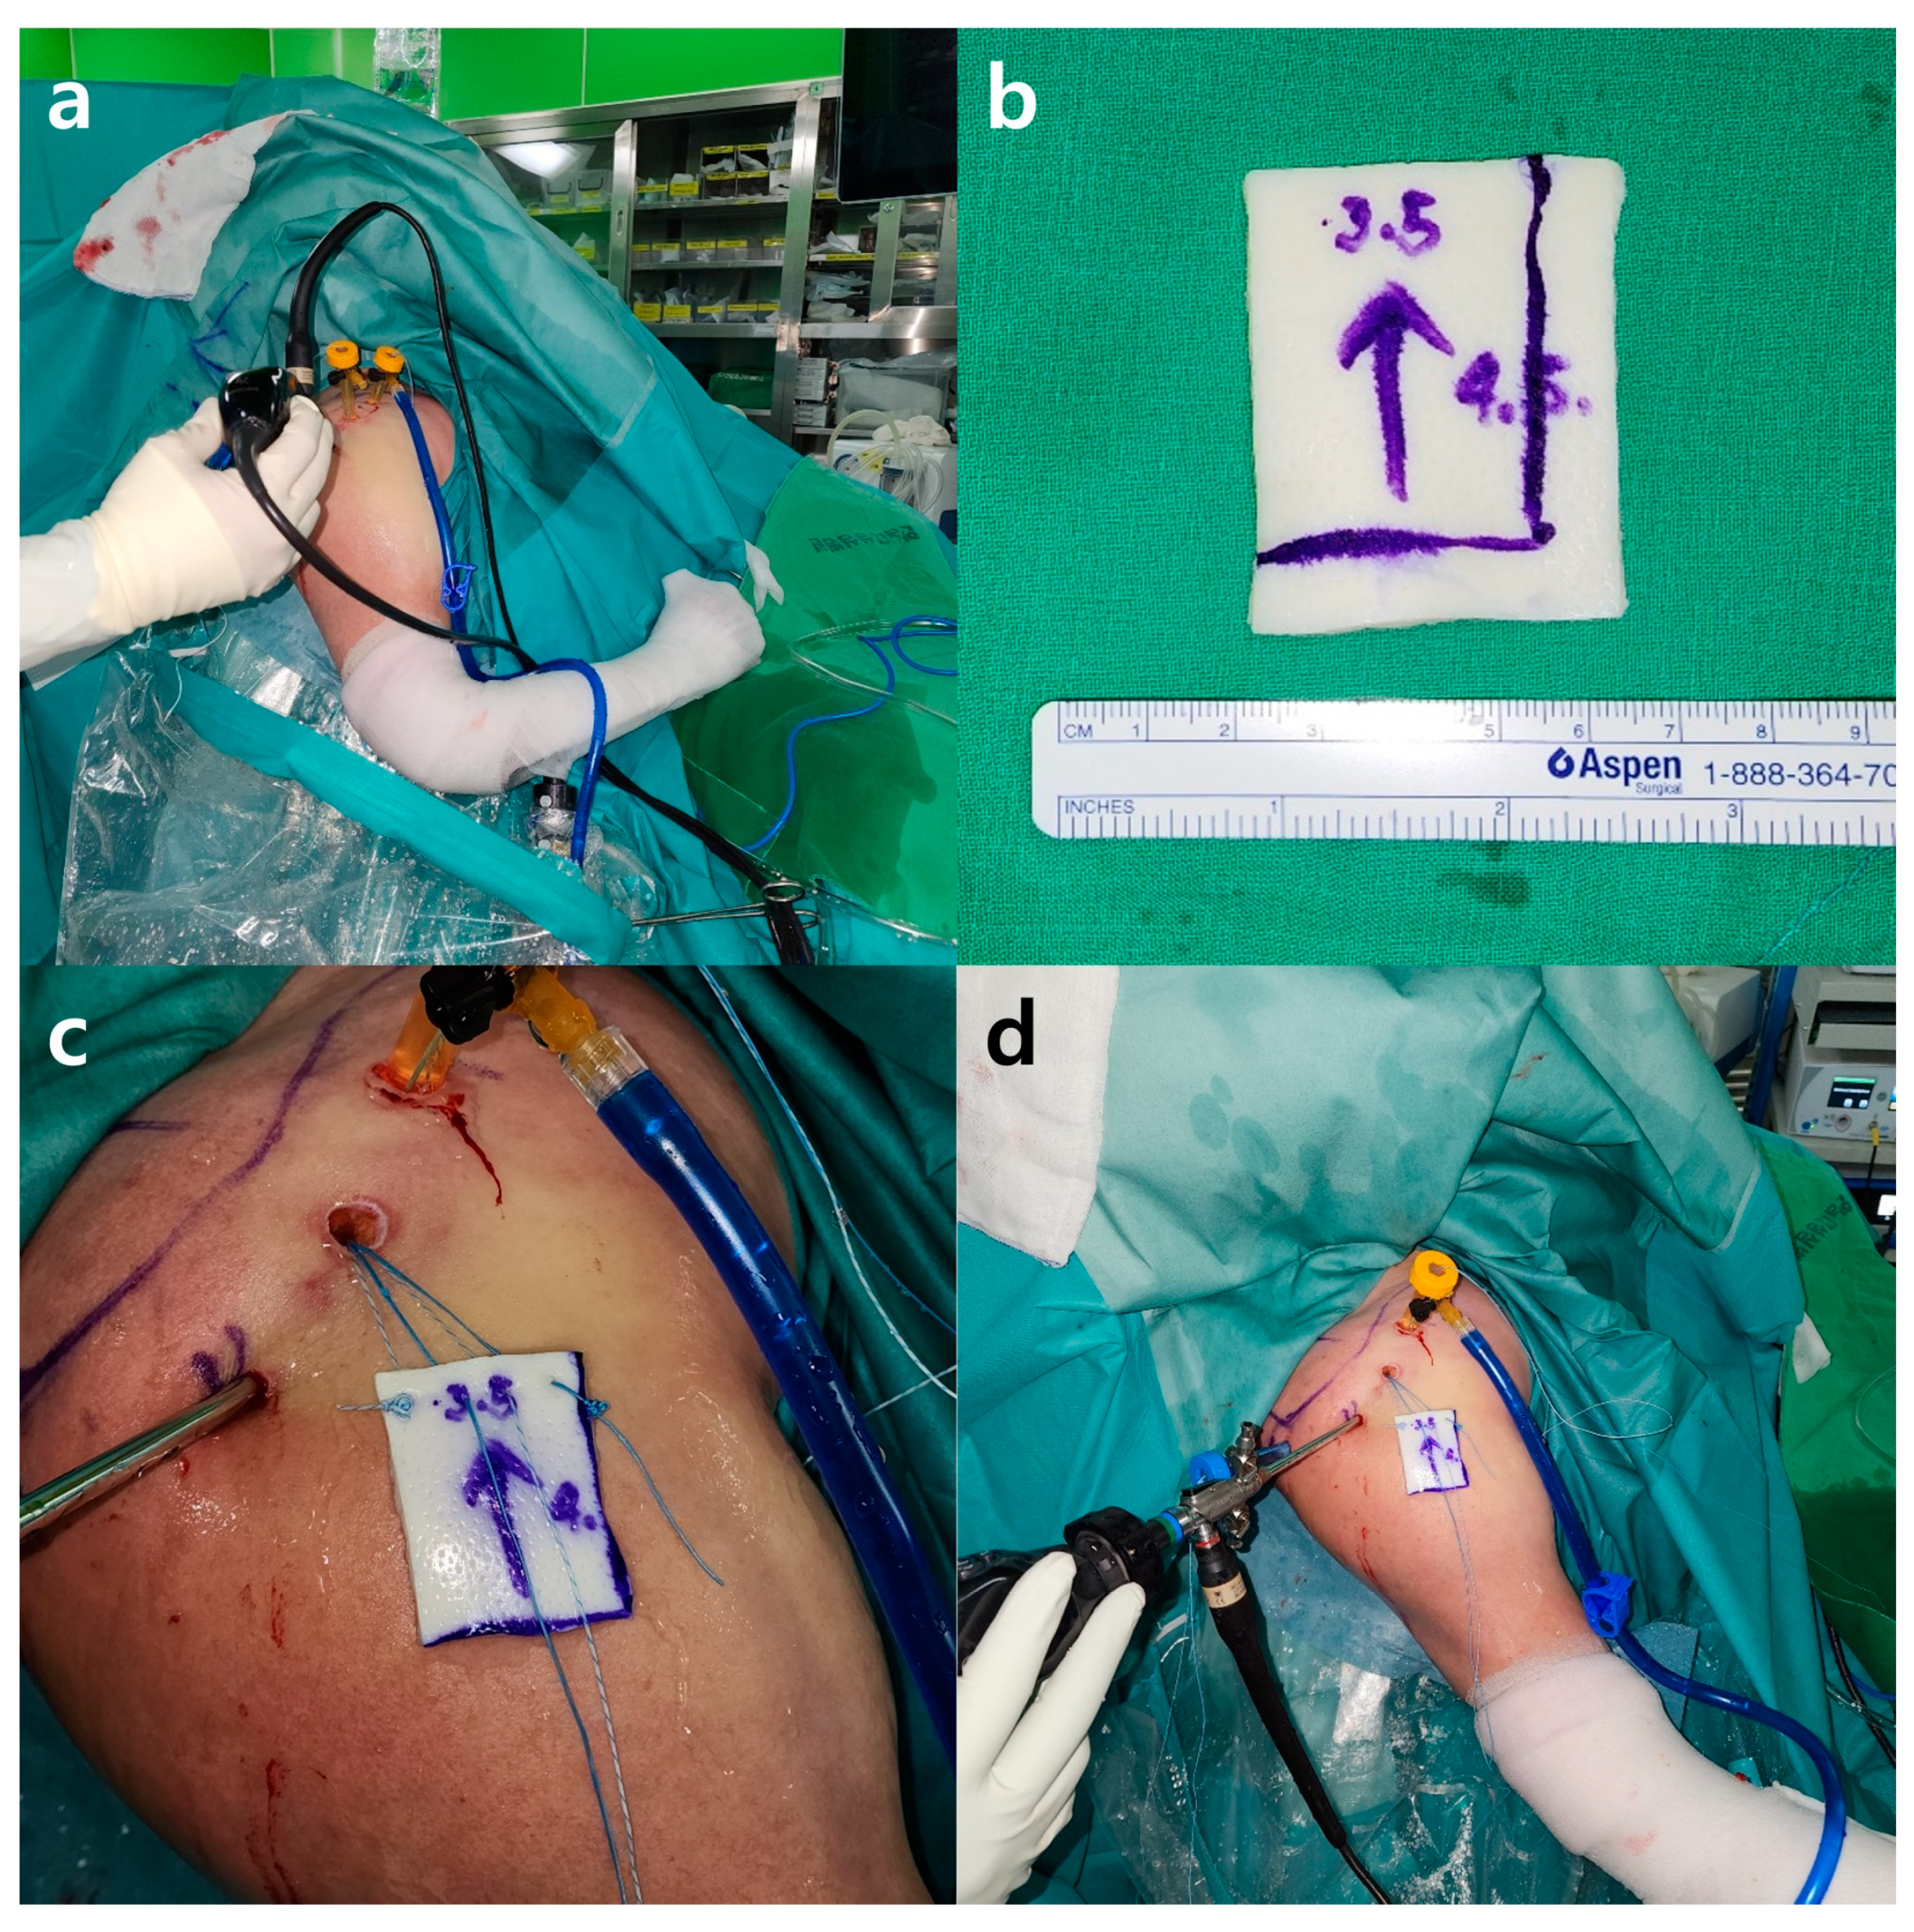

2.5. Surgical Technique

2.5.2. Superior Capsule Reconstruction

2.5.3. Patch Graft Augmentation